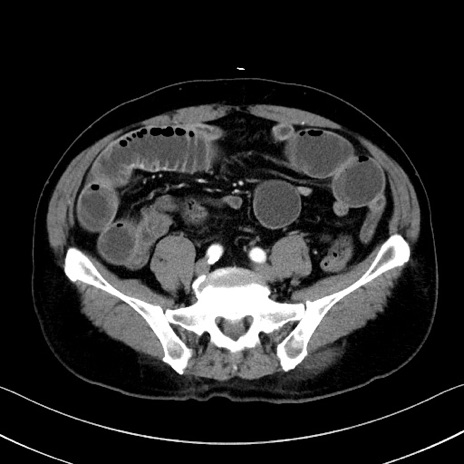

症例35(横断像)

【症例】70歳代 男性

【主訴】腹部膨満、嘔吐

【現病歴】昨日より腹部膨満感出現。本日増悪し、仙痛出現。嘔吐あり、受診。

【既往歴】糖尿病、胆摘後

【身体所見】BP 149/80mmHg、HR 74/min、BT 35.9℃、腹部:膨満、軟、圧痛なし。腸雑音減弱あり。上腹部正中切開瘢痕あり。

【データ】WBC 13500、CRP 1.72